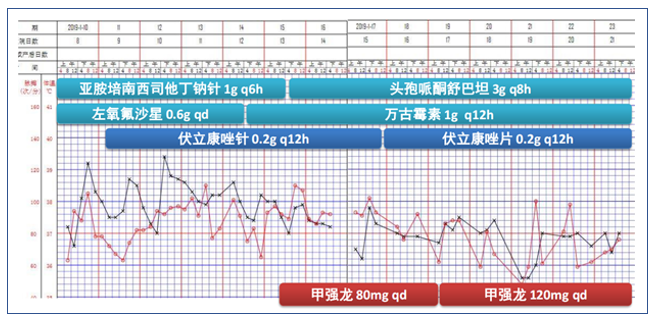

病情发展

图3 患者初始治疗方案及生命体征变化情况

病情进一步发展

2019年1月10日,再次高热39.1℃,无伴明显畏寒、寒战;间伴有烦躁发作。患者1月10日后反复发热,氧合变差,多次肺部影像学提示;双肺多发渗出灶较前进展。Cstat(呼吸系统静态顺应性)22-30,肺顺应性差。

根据患者临床表现及检查结果,再次调整治疗方案(图10)。

调整治疗方案

根据患者情况又调整了治疗方案(图13)。患者2月11日拔管脱机,再次出现高热,谵妄反复发作,胡言乱语,对外周刺激敏感,伴气促、低氧(SpO2:75%~85%)。